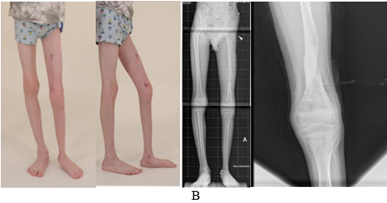

Следует отметить, что пациент в анамнезе получал лишь консервативное лечение по месту жительства и использовал ортопедическую обувь с подбивкой на имеющуюся величину укорочения. Ребенок поступил с жалобами на деформацию, укорочение левой нижней конечности и деформацию левой стопы, что вызывало у него значительное ограничение передвижения (4 уровень по шкале Gillette [11]). Объективно у данного пациента определялся перекос таза влево, укорочение левой нижней конечности на 8 см за счет бедренной и большеберцовой костей равномерно, вальгусно-антекурвационная деформация диафиза большеберцовой кости, вальгусная деформация щели голеностопного сустава с гипоплазией и эквинусной деформацией левой стопы (рис. 1, А).

Рис. 1. Фото и рентгенограммы пациента до (А), в процессе (Б) и после реконструктивного ортопедического лечения (В).

Данный пациент получал реконструктивное ортопедическое лечение поочередно в два этапа (1 этап – голень и стопа, 2 этап – бедро) с целью коррекции деформации и удлинения больной конечности с использованием метода Илизарова и метода управляемого роста (дистальный отдел большеберцовой кости), включая резекцию фиброзно-хрящевого рудимента малоберцовой кости, удлинения сухожилий малоберцовых мышц, ахиллотомию и тенодез задней большеберцовой мышцы левой голени (рис. 1, Б). Удлинение левой нижней конечности выполнено на 8 см, индекс остеосинтеза составил 37,4 дня/см. Осложнений, таких как воспаление мягких тканей в области спиц, контрактур смежных суставов, перелома зоны регенерата, у данного больного не было. На контрольном осмотре через 1 год после лечения пациент и его семья были довольны результатом лечения. Ребенок передвигался самостоятельно, клинически движения в тазобедренном и коленном суставах были в полном объеме, движения в левом голеностопном суставе отмечались с амплитудой 30º, вальгусная девиация левой стопы уменьшилась (продолжался временный дистальный медиальный гемиэпифизиодез большеберцовой кости 8-образной пластинкой для коррекции положения щели голеностопного сустава в процессе роста ребенка (рис. 1, В)). Однако ввиду прогрессирования заболевания определялась разница в длине нижних конечностей 2 см, которую ребенок компенсировал подбивкой под обувь (рис. 1, В). Уровень двигательной активности пациента через 1 год после лечения оценен по шкале Gillette 8-м уровнем.